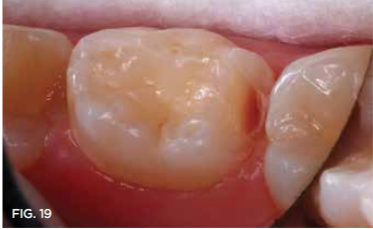

Case 3. This 10-year-old boy was brought to the office for a second opinion regarding restoration of the left primary first molar, which was causing sensitivity (Figure 8). The boy's mother reported that a "tooth-colored filling" had been suggested at another office. The boy was terrified of needle injections and, according to his mother, had required sedation in prior years for restoration of maxillary primary molars. SDF was applied (Figure 9), tooth sensitivity was eliminated, and in 3 months, clinical evaluation and a periapical radiograph confirmed that no other treatment would be needed until the tooth exfoliated (Figure 10 and Figure 11).

Fig 19. Caries lesion exposed with diamond bur slice.

Fig 19